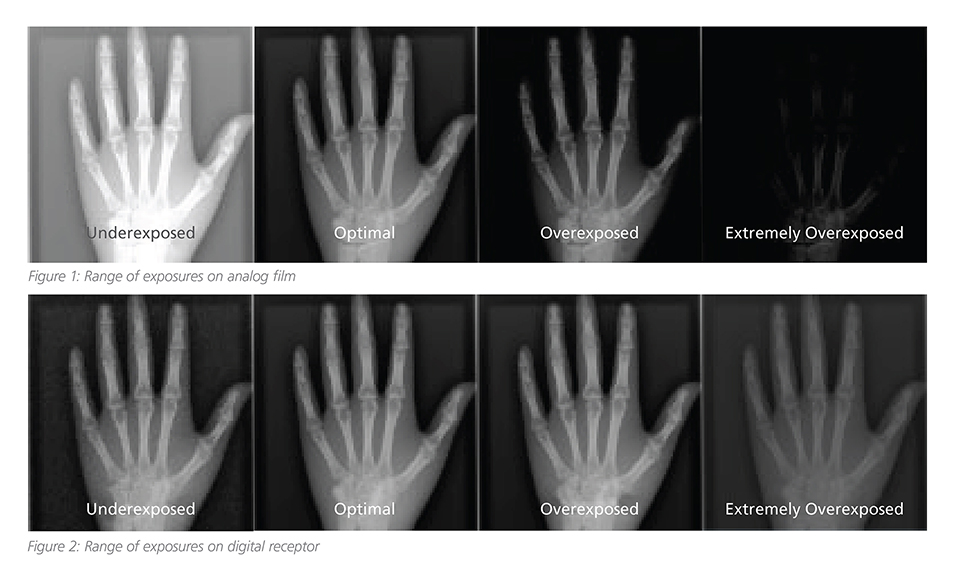

Exposure Indices, Dose, and Image Quality

Alright – let’s admit it, X-Ray Machines are pretty smart these days. So smart, in fact, they can adjust hardware and technique settings automatically [...]

CARESTREAM Image Suite V4 MR11 has set a new standard for workflow efficiency, offering a robust set of features and functionalities to enhance clinical confidence in healthcare professionals. Using an auto-generated companion image from a single exposure, leverage a range of image processing options to increase diagnostic accuracy and enhance patient care.

Our Carestream Focus HD 35/43 Retrofit Detectors, powered by Image Suite Software, are an ideal solution to step up to full digital X-ray for customers who simply cannot compromise on image quality. It seamlessly integrates into existing setups, bringing the power of full digital X-ray with minimal disruption and maximum clarity, along with the following benefits: